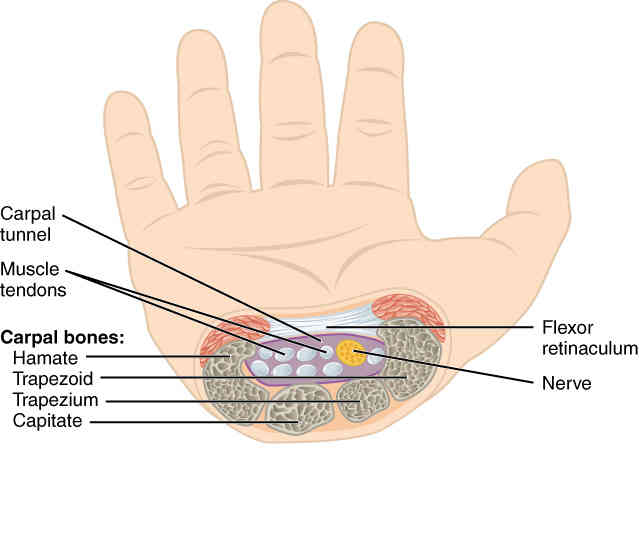

This page is under construction. For now, it is just a resource of the images found in the OpenStax Anatomy and Physiology Handbook. It wil slowly change into a revision tool. Each slide has a number. Use this to refer to the slide. When completed, it will have an unlabelled section, with labelled slides in parallel. On the unlabelled slides, write your answer and use the labelled slide to assess yourself. Keep track by also noting the number on each slide. Improvement at each attempt is important, more so than full marks on a first attempt.